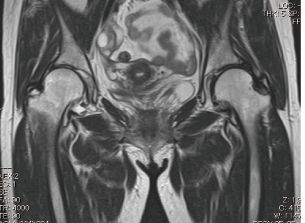

MRIでわかる“隠れた股関節の異常”

MRIでは、レントゲンに写らない軟骨や筋肉、関節唇の状態を立体的に確認できます。

たとえば、次のような異常が判明するケースがあります。